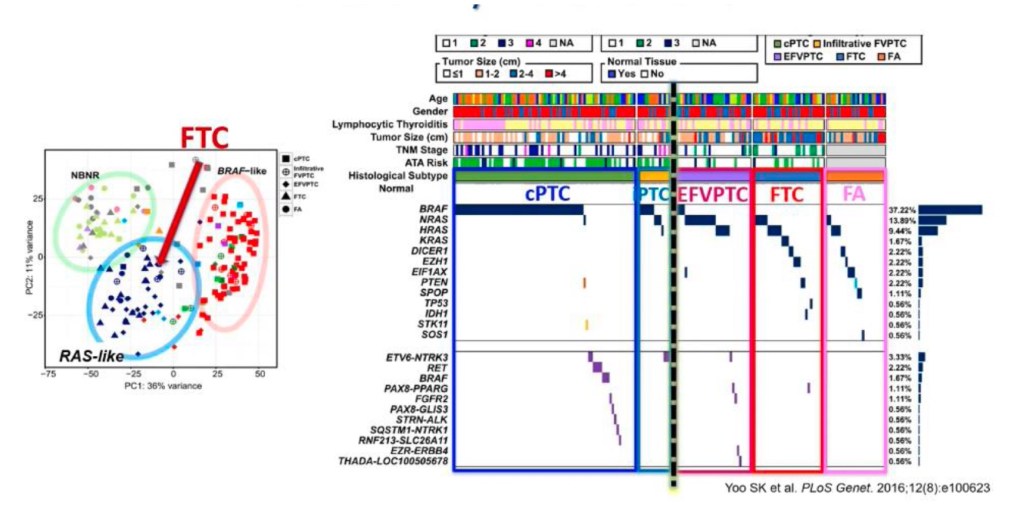

The RET proto-oncogene is located on chromosome 10. A genetic mutation in the RET oncogene is seen in all cells in the body in patients with the hereditary forms of MTC. Mutations in RET can also be seen only in the tumor cells in patients with sporadic MTC. Since the discovery of the RET oncogene, more than 100 different mutations have been identified in the gene in patients with MTC.